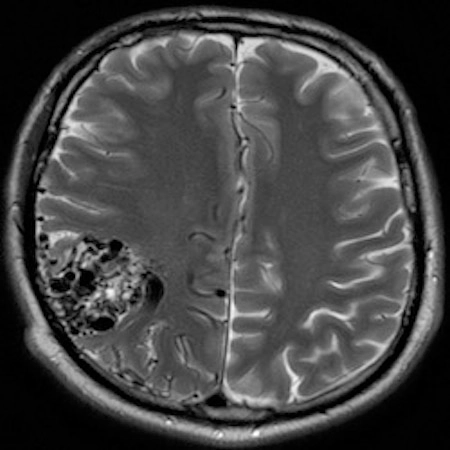

Brain Arteriovenous Malformation © 2025 by Daniel Walsh is licensed under CC BY-ND 4.0